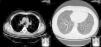

Two weeks later, the patient presented clinical improvement (after drug treatment with antibiotics and bronchodilators) but with persistent injury in chest radiography, so a thoracic CT was performed, showing bilateral and diffuse ground-glass opacities, multiple centrilobular micronodules (Fig. 1) and mediastinal lymphadenopathy. Bronchoscopy was normal, and transbronchial biopsy showed the presence of non-necrotizing granulomas. Ziehl Neelsen, and Groccott staining were negative, as PCR and mycobacteria culture. After completing HCV treatment, the clinical course of the patient was favorable, showing the following thoracic CT gradual improvement in lung and lymph node involvement, and finally, a year later, the resolution of the disease (Fig. 2).